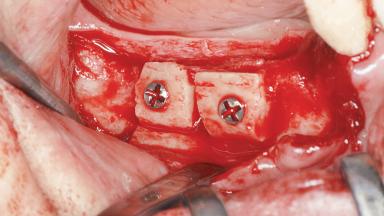

A woman in her mid-fifties was referred by a dental student for dental implant placement. Both posterior segments of the mandible had been edentulous for more than 4 years, the only residual tooth being the right lower first premolar. The patient had used a removable partial denture but was not entirely satisfied with its function. The clinical examination revealed a sharp edentulous ridge in both posterior segments of the mandible, and the patient was told that it would not be possible to insert implants into this thin edentulous ridge without significant augmentation of the alveolar ridge. Her medical history revealed no significant findings and no underlying disease that might have complicated surgical procedures. During the presurgical examination, the patient reported that she was a little apprehensive about bone grafting. After being informed about the surgical procedures and potential postoperative complications, she accepted the proposed surgical plan of bone grafting and subsequent placement of implants.

| Bone Volume | Deficient horizontally, requiring prior grafting |